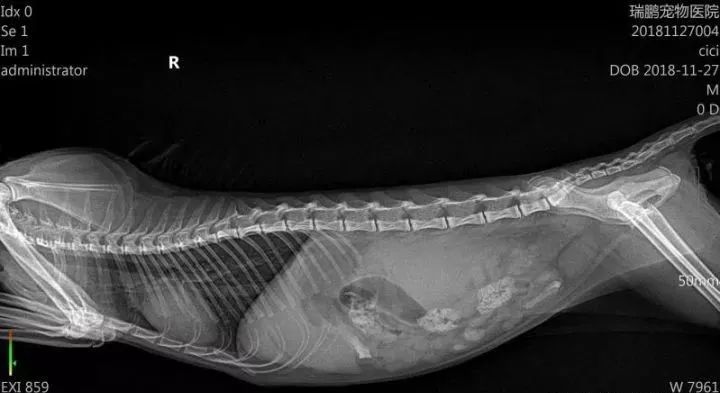

在11月25号我带它去宠物医院,拍片—抽血。

于是我转战到另外一个宠物医院,医生接手了,于是又一次化验-做B超及其他检验,隔天才有结果,等到第二天,医生告诉我是“肾脏大”